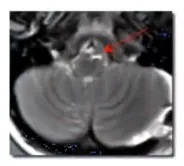

她的世界开始倾斜:看东西重影,头晕袭来,走路时身体不受控制地左右摇晃,每一步都走得蹒跚艰难。医院给出了诊断:脑干海绵状血管瘤。那些医学术语——复视、共济失调、步态障碍——背后,是一个年轻女孩正在摇晃的年轻生命。

吉娜术前MRI

脑干海绵状血管瘤,即时在当时世界范围内甚至都没有很多病例报道,更别说成功手术案例。这种疾病的名字里虽然带了个“瘤”字,但它本质上是一种血管畸形,属于良性病变。这意味着,如果能被安全地完全切除,患者有很大机会恢复正常生活。然而,这个“如果”背后是巨大的风险——脑干是生命中枢,手术犹如在钢丝上跳舞,一旦失误,后果不堪设想。